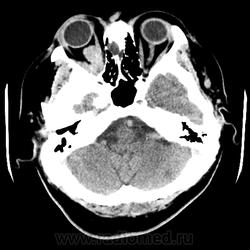

Женщина 48 лет, поступила с подозрением не ОНМК. На КТ -данных за ОНМК не обнаружено, но в правой орбите ретробульбарно мягкотканное образование +45HU, признаков деструкции и ремоделирования костных структур орбиты не наблюдается, медиальная и нижняя прямая мышца отчетливо не дифференцируются, зрительный нерв тесно прилежит к данному образованию. После КУ гомогенное накопление КВ и повышение плотности до +65HU. Экзофтальм. Жалобы на снижение зрения. Год назад делала МРТ ГМ, на снимке патологии орбит не увидел. Идиопатическая псевдоопухоль орбиты?

В мягких тканях носогубного треугольника справа тоже образование.

Натив

На первое место все же поставила бы гемангиому. Локализация, возраст, пол, флеболит, случайная находка, безболезненный экзофтальм, ремоделирование стенок орбиты -это за гемангиому.

Кавернозная гемангиома? Ремоделирования стенок орбиты как раз таки нет, они интактны. Должна быть псевдокапсула, а здесь больше похоже на инфильтрацию прямых мышц, я за псевдоопухоль.